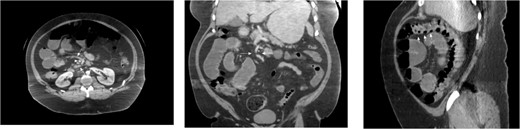

A 59-year-old female presented to our clinic with 10 years of vague episodic abdominal pain without prandial association. These episodes varied in severity, were self-limiting, and were not provoked by any identifiable factor. Her history was significant for asthma, GERD, and previous abdominal hysterectomy. The patient’s abdominal exam revealed only a Pfannenstiel scar but no tenderness, hernia, or palpable mass. The patient did not endorse any active symptoms in clinic. The patient underwent a CT scan of the abdomen and pelvis with IV and PO contrast which demonstrated small bowel loops in the right upper quadrant suspicious for herniation into a left paraduodenal space. Outpatient CT scan images can be found below (Fig. 5). The patient was scheduled for a diagnostic laparoscopy to evaluate for a paraduodenal hernia. Dense and extensive adhesive disease necessitated conversion to an upper midline laparotomy. The patient was found to have a left-sided paraduodenal hernia with the entire jejunum contained within Landzert’s fossa but without any signs of active obstruction. Additionally, the patient was found to have malrotation of the large bowel. After successful reduction of the non-obstructed small bowel, the mesenteric defect was then closed with a running silk stitch and the nearby proximal jejunum tacked over the repair. The malrotated large bowel was also placed in its correct anatomical position. The remainder of the procedure was uncomplicated with the patient recovering well.

CT images for Case 3, axial, coronal, and sagittal, respectively. The isolation of the contrast-filled small bowel can be appreciated in the right upper quadrant, representing bowel entrapped within the left paraduodenal hernia.